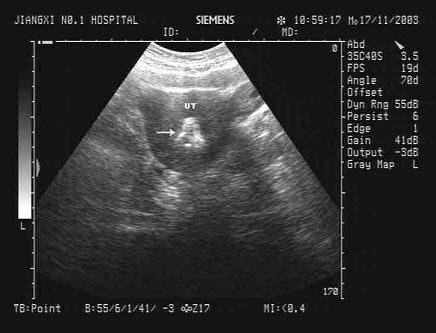

32、单项选择题

女性,27岁,停经45天,阴道不规则出血1周余。尿妊娠试验阳性。结合超声图像,最可能的诊断为()